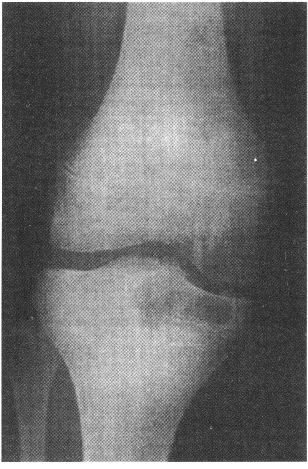

4.男,17岁。右膝关节疼痛1个月余,轻度肿胀。X线片示胫骨近端圆形骨质破坏(如图),应考虑的诊断是![]() |

| 正确答案:C 解题思路:骨结核大多数继发于肺结核。结核杆菌经血行到达骨或关节,停留于血管丰富的骨松质内而发病,病理上表现为渗出、变质和增殖。 |